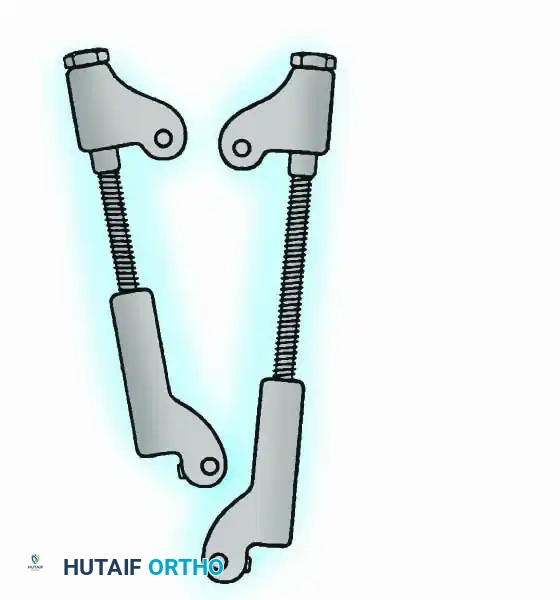

Historically pioneered by Charnley, external compression arthrodesis utilizes pins placed through the distal tibia and the body of the talus. Because Charnley's original uniplanar device lacked rotatory stability, Calandruccio designed a triangular frame to control motion in all three planes while applying massive compression.

Modern iterations, such as the Calandruccio II compression device, offer greater latitude in pin placement to avoid compromised skin. Ring or circular external fixators (Ilizarov, Taylor Spatial Frame) are the gold standard for salvage situations, including active infection, massive bone loss, or failed TAA, as they allow for simultaneous compression, deformity correction, and early weight-bearing.